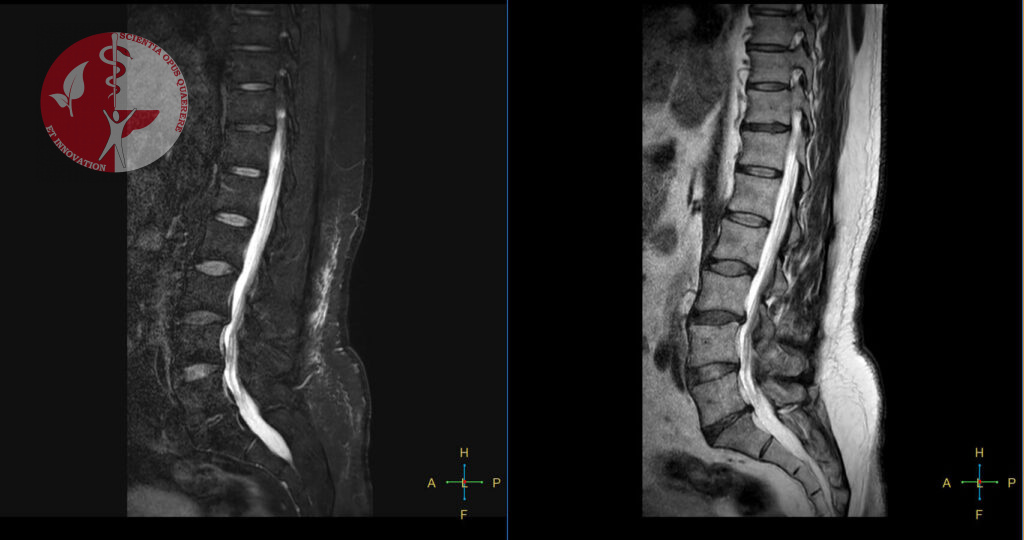

Благодаря обследованию можно выявить межпозвоночные грыжи, кисты, опухоли, различные дегенеративные изменения, аномалии развития, воспалительные заболевания, сосудистые аномалии.